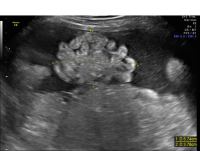

Gastroschisis

Gastroschisis, which is a type of “ventral wall defect,” is diagnosed when some of the contents of the abdomen protrude out of the body through an opening in the abdominal muscles near the umbilical cord. Having no protective covering, the organs are exposed to amniotic fluid and can become swollen or damaged. Gastroschisis occurs in approximately one in 5,000 births and is typically an isolated birth defect.

Gastroschisis free bowel